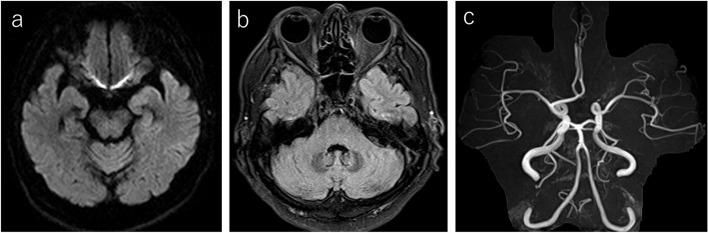

A 70-year-old man was referred to our hospital due to diplopia that manifested 1 week after receiving the second Moderna vaccine dose. The patient presented with restricted abduction of both eyes, mild ataxia, and loss of tendon reflexes. He was diagnosed with MFS based on his neurological findings and detection of serum anti-GQ1b antibodies. The patient was administered intravenous immunoglobulin, and his symptoms gradually improved. Five days after admission, the patient showed peripheral facial paralysis on the right side. This symptom was suggested to be a delayed onset of peripheral facial nerve palsy following MFS that gradually improved by administration of steroids and antiviral drugs.

一名 70 岁男性因接种第二剂 Moderna 疫苗后 1 周出现复视而被转至我院。患者表现为双眼外展受限、轻度共济失调和腱反射消失。根据他的神经学表现和血清抗-GQ1b 抗体的检测,他被诊断为 MFS。患者接受了静脉注射免疫球蛋白治疗,症状逐渐改善。入院后 5 天,患者出现右侧周围性面瘫。该症状提示 MFS 后发生的周围性面神经麻痹延迟发作,通过给予类固醇和抗病毒药物治疗后逐渐改善。